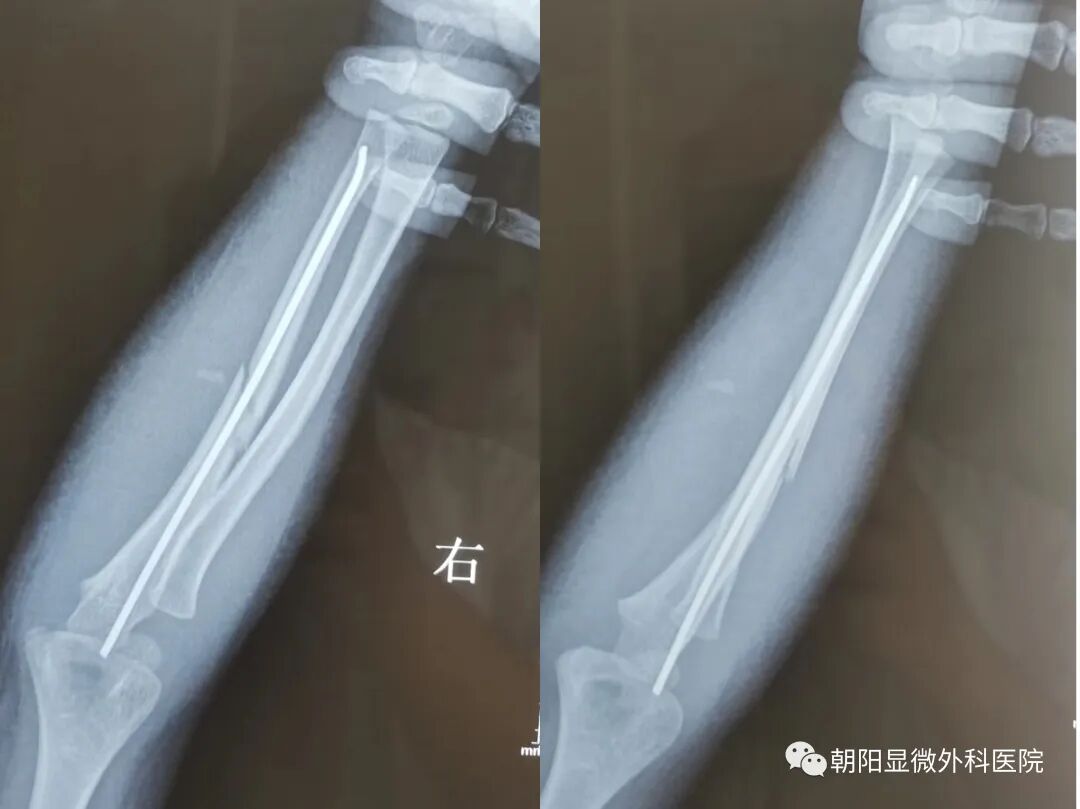

手术后

术后25天复查

儿童前臂骨折,髓内固定时切口小,损伤小,切口美观。

髓内钉固定为弹性固定,手术后要行石膏外固定。符合“稀松内固定,坚强外固定”的理念。

手术后石膏托固定4周,开始行肘关节屈伸锻炼和前臂旋转锻炼